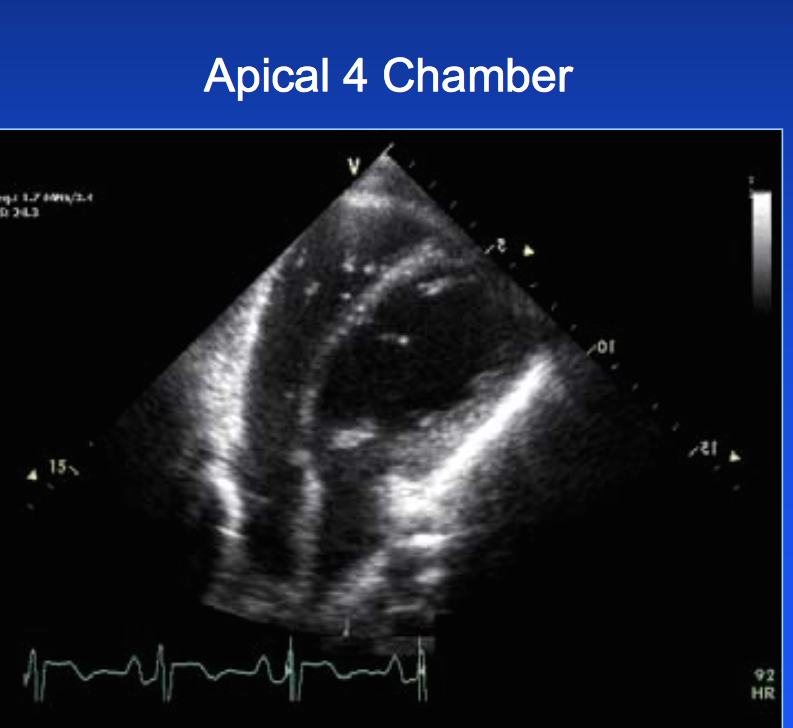

Dx?

congenital abscence of pericardium (notive RV dominating apex and teardrop shape)